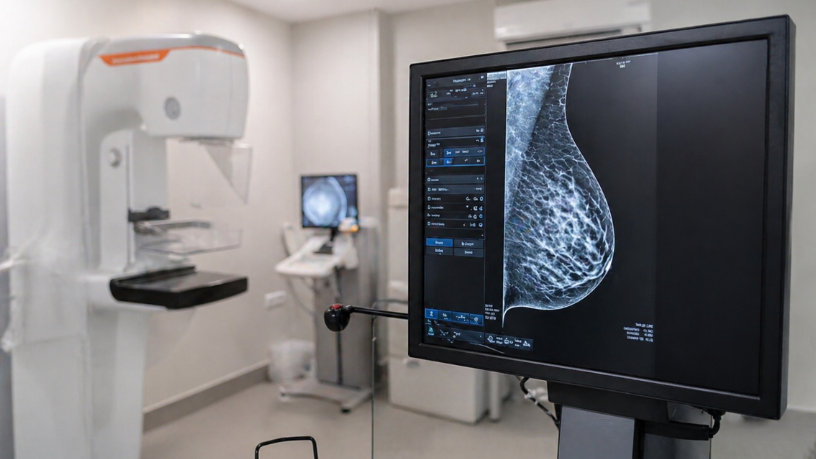

Um dos principais avanços está na mamografia digital. Diferente do modelo tradicional, ela permite capturar imagens com maior qualidade e facilitar o armazenamento e a comparação ao longo do tempo. Isso contribui para uma análise mais detalhada e melhora a capacidade de identificar alterações sutis. Com imagens mais nítidas e organizadas, o acompanhamento evolutivo se torna mais preciso e confiável.

Outro destaque é a tomossíntese mamária, também conhecida como mamografia 3D. Segundo Vinicius Tadeu Sattin Rodrigues, essa tecnologia cria imagens em diferentes camadas da mama, permitindo uma visualização mais completa dos tecidos. Esse recurso reduz sobreposições que podem dificultar a leitura e aumenta a precisão na identificação de possíveis anormalidades. Como resultado, há maior clareza na interpretação e redução de dúvidas durante a análise.

Além disso, a integração com sistemas digitais permite ajustes de contraste e ampliação de áreas específicas. Essa flexibilidade melhora a visualização de detalhes que poderiam passar despercebidos em exames convencionais. O resultado é uma análise mais minuciosa e confiável. Esse nível de detalhamento contribui para decisões mais seguras e um diagnóstico mais assertivo.